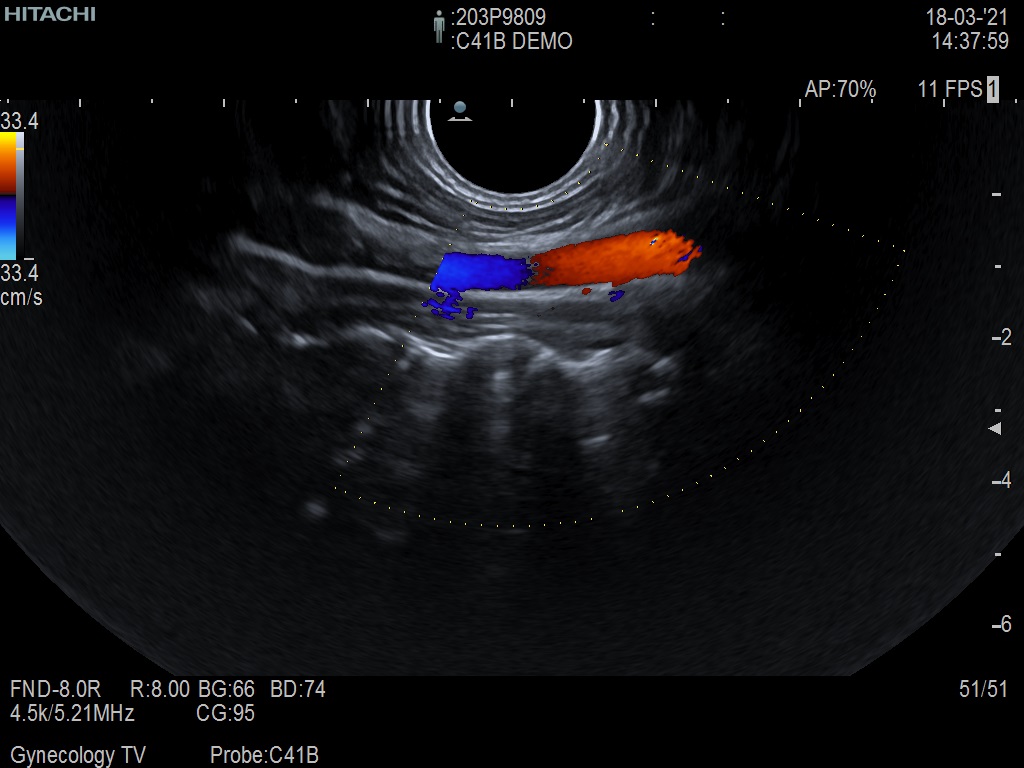

Hitachi C41B DEMO Endocavity Vaginal – ARIETTA

ARIETTA Endocavity C41B

Angled End-fire Endocavity

Hitachi C41B Endocavity Vaginal – ARIETTA

Frequency Range: 10 – 2 MHz

Scan Width: 10 mm Radius

Scan Angle: 200° FOV

Hitachi C41B Endocavity Vaginal/Rectal – ARIETTA for Angled End-fire Obstetric, Gynecology and Endorectal

| Ακτινολογικές λειτουργίες | Contrast Harmonic Imaging (CHI), Elastography (RTE), RT Sonography (RVS) |